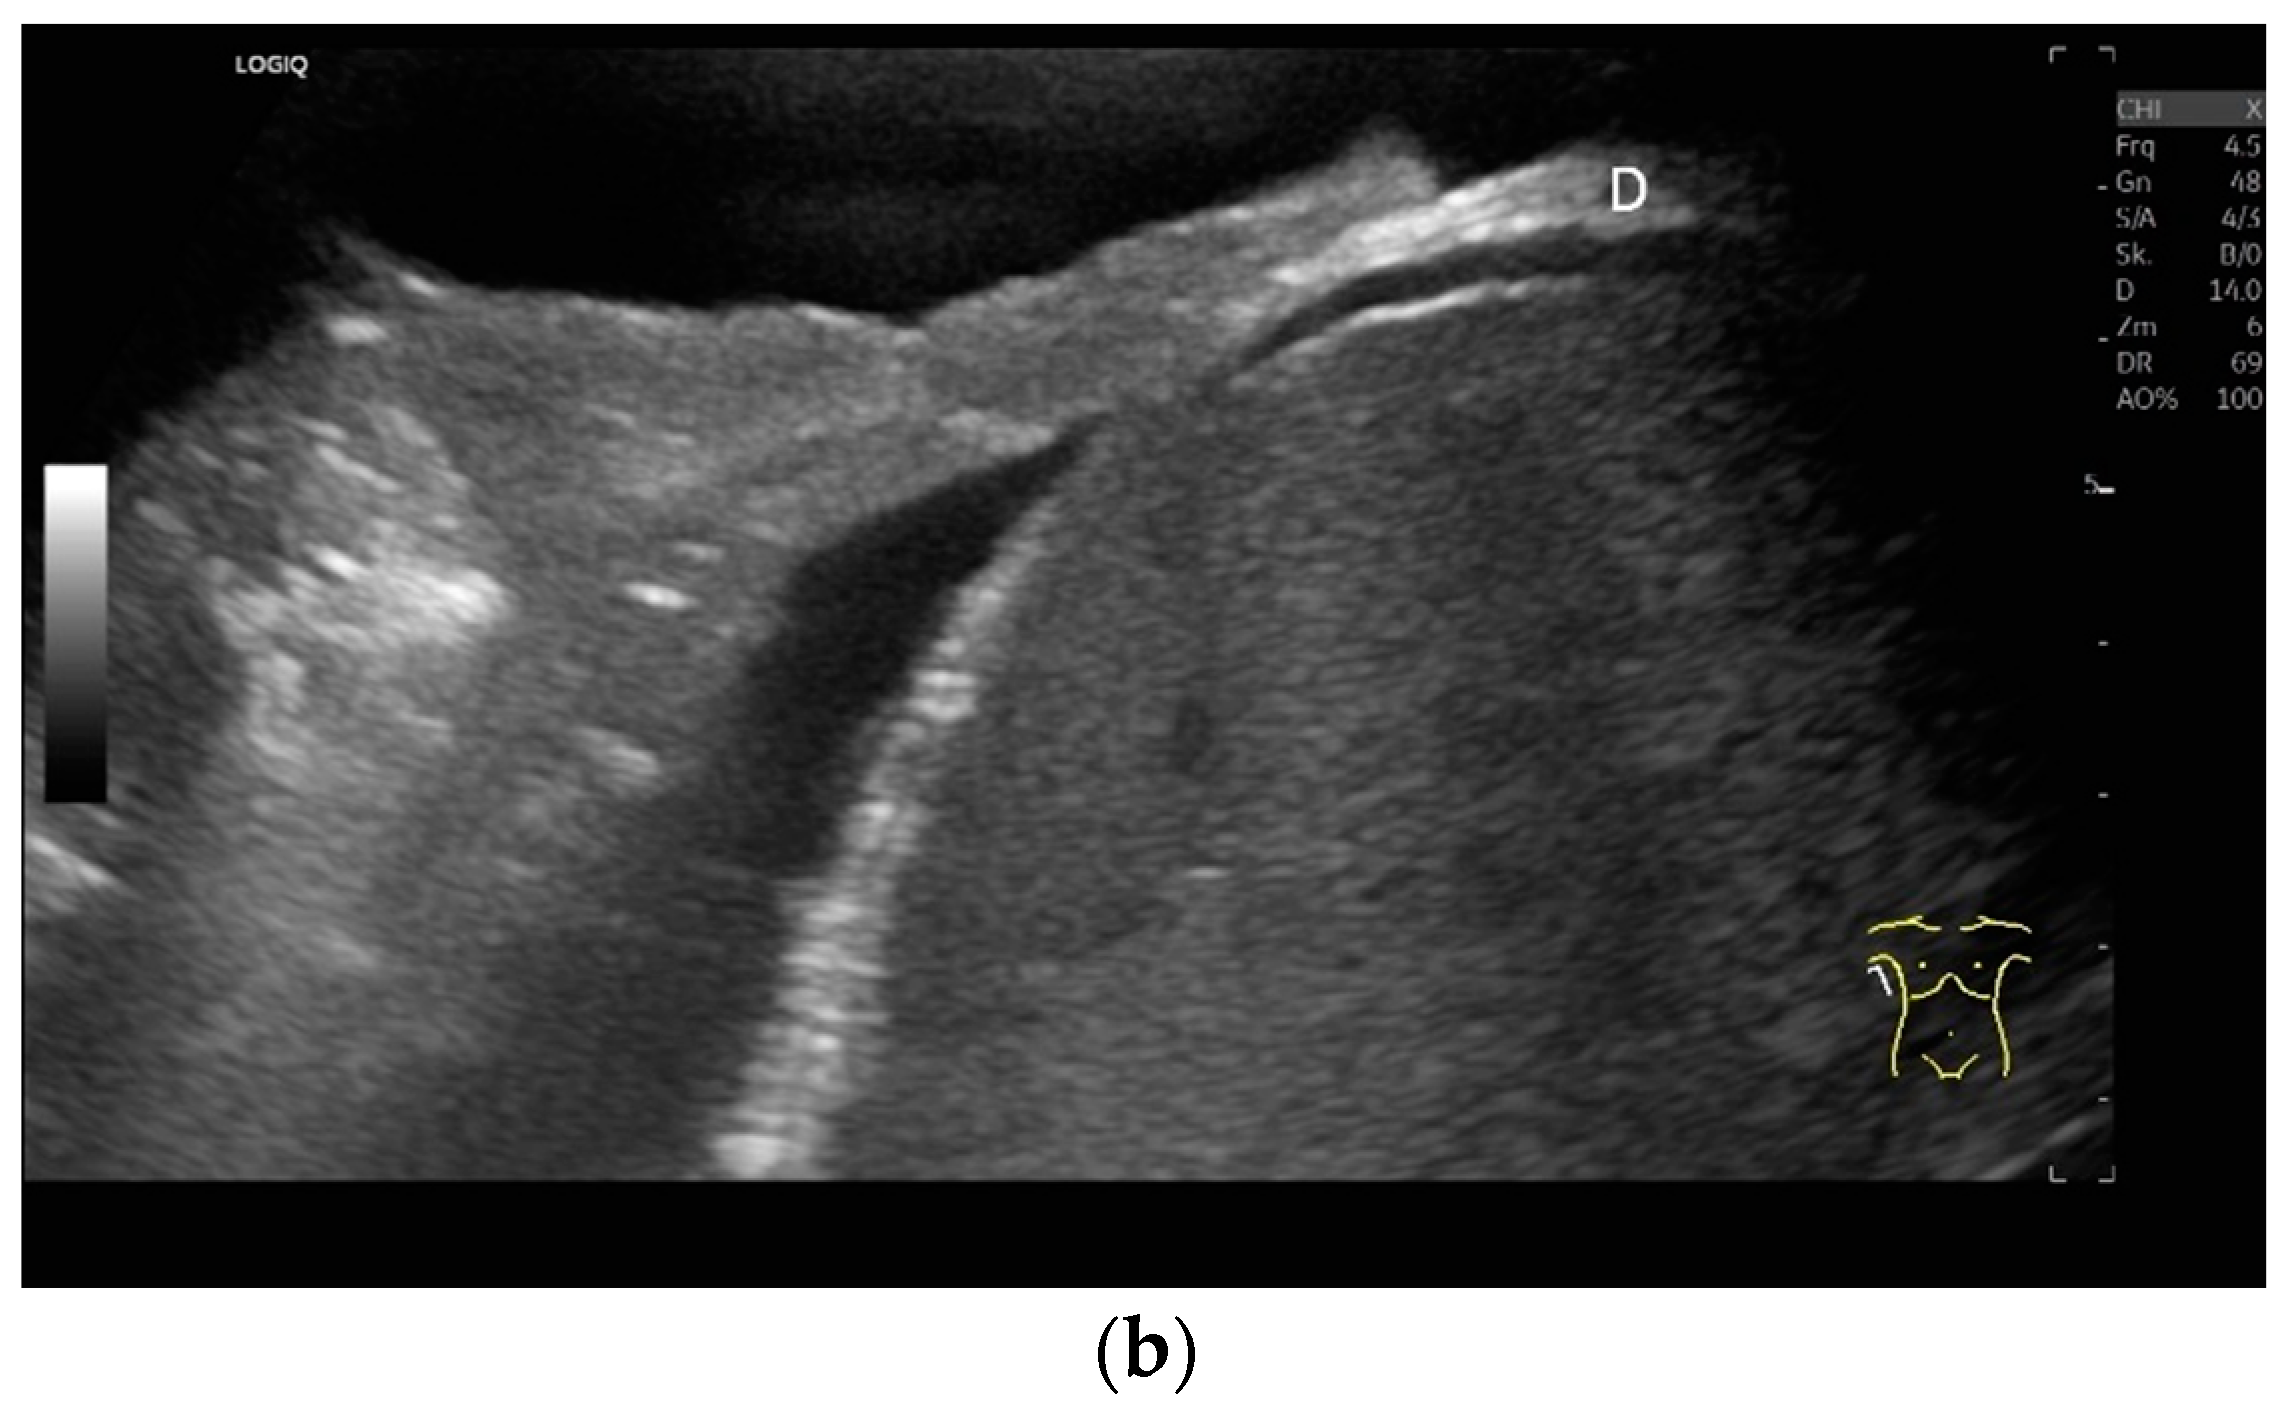

Subxiphoid: The diaphragm can be positioned directly subxiphoidally with a slightly sagittal transducer position on both sides next to the attachment to the sternum. The diaphragm limb can be demarcated to the right in the epigastrium in cross section between the aorta and the inferior vena cava. However, this is primarily of differential diagnostic importance, e.g., in relation to lymphomas, not for the actual assessment of the diaphragm (Figure 6).